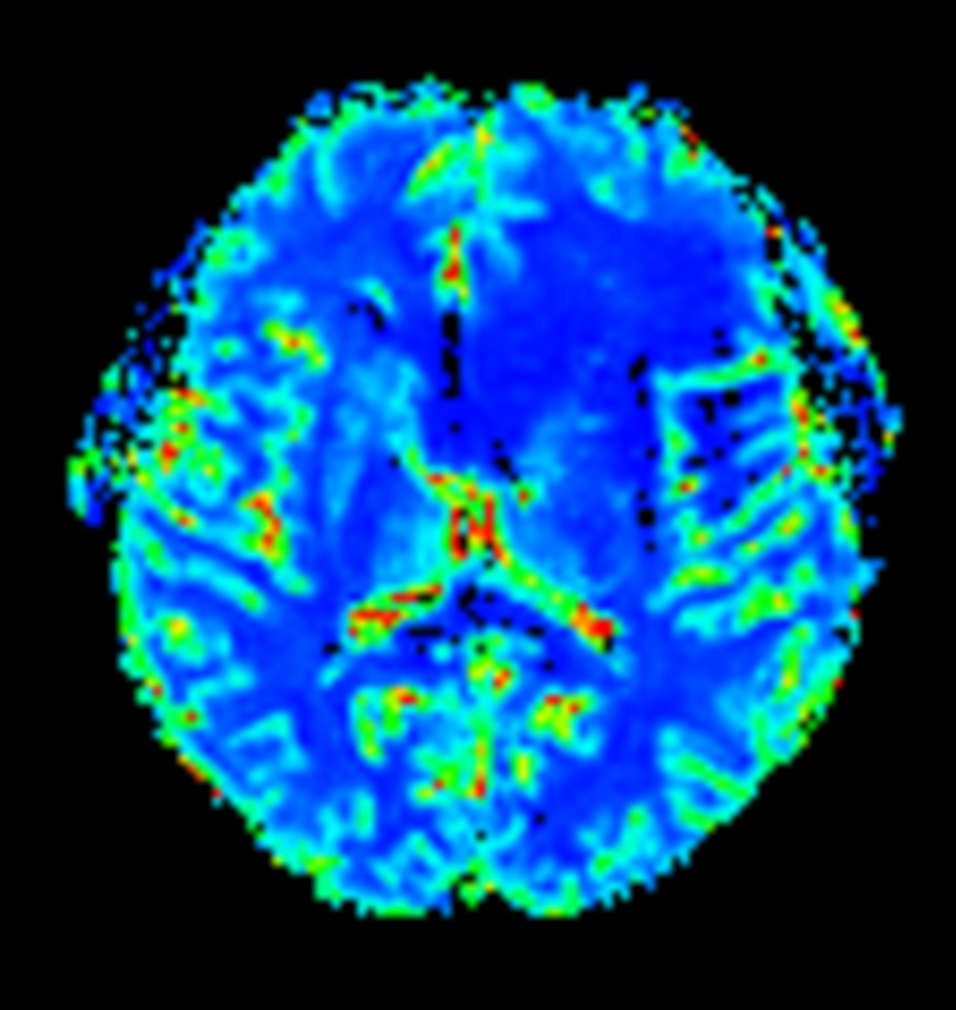

T2* Perfusion (Index)